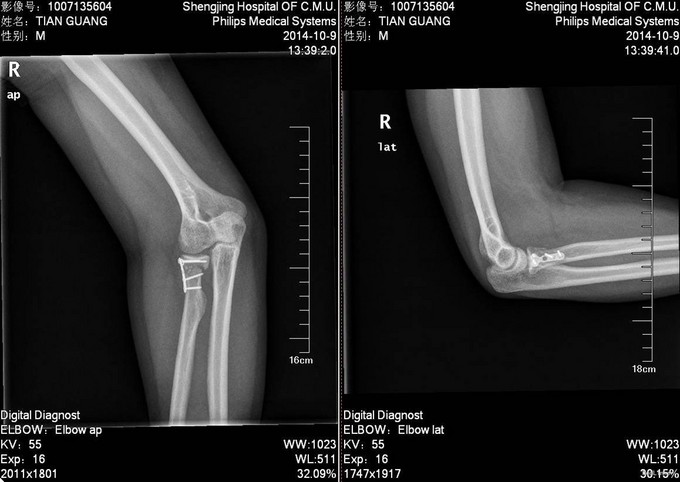

患者6小时前不慎摔倒,右手着地,当时即感右肘部剧烈疼痛,活动受限,被家人急送往奉天医院急诊,拍片检查示:右桡骨近端骨折,以“右桡骨骨折”收入院,现为进一步诊治,来我院就诊,以“右桡骨骨折”收入院,患者病来无头晕头痛,无恶心呕吐,无咳嗽咳痰,无发热寒战,饮食睡眠正常,二便正常,体重无明显减轻。

患者平车推入病房,右上肢甲板固定中,右肘部疼痛,压痛(+),可触及骨擦音,骨擦感,无明显淤血瘀斑,患肢末端血运可,右上肢皮肤感觉较健侧无明显异常,手指可活动,右桡动脉可触及搏动。

入院后完善检查,查无手术禁忌症后行右桡骨颈骨折切开复位内固定术,术后抗炎、接骨等对症治疗。术后第二天康复锻炼。术后2天一次换药,14天后出院。